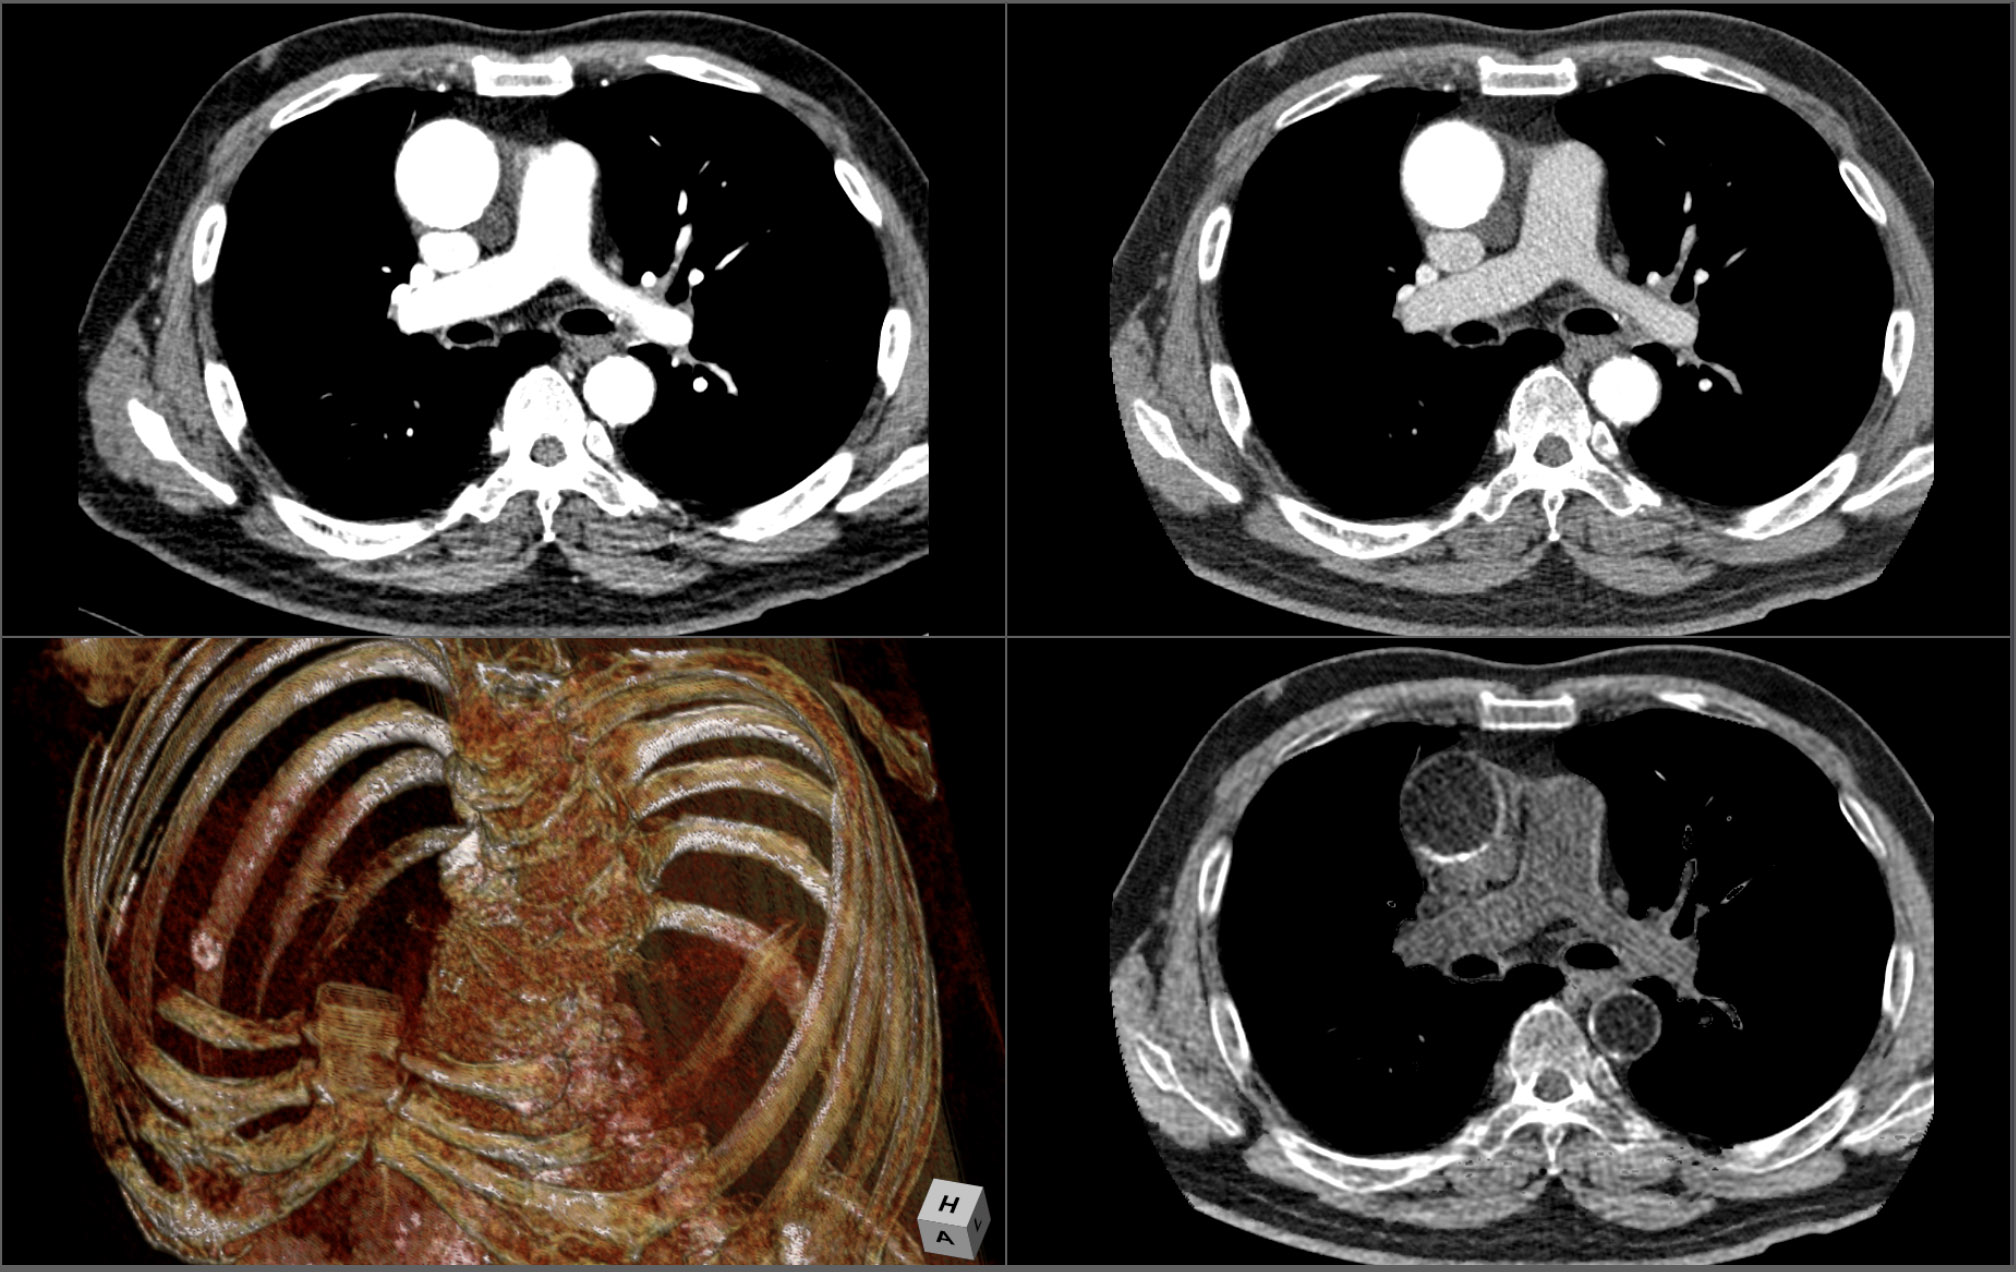

3D ANALYSIS

Ziostation2 handles the growing dataset sizes with ease, displaying high-definition Volume Rendered images, along with MPR, CPR, MIP, MinIP, SUM, VE and Gradient MIP data visualizations. All tools can be accessed immediately with top-level GUI selection controls.